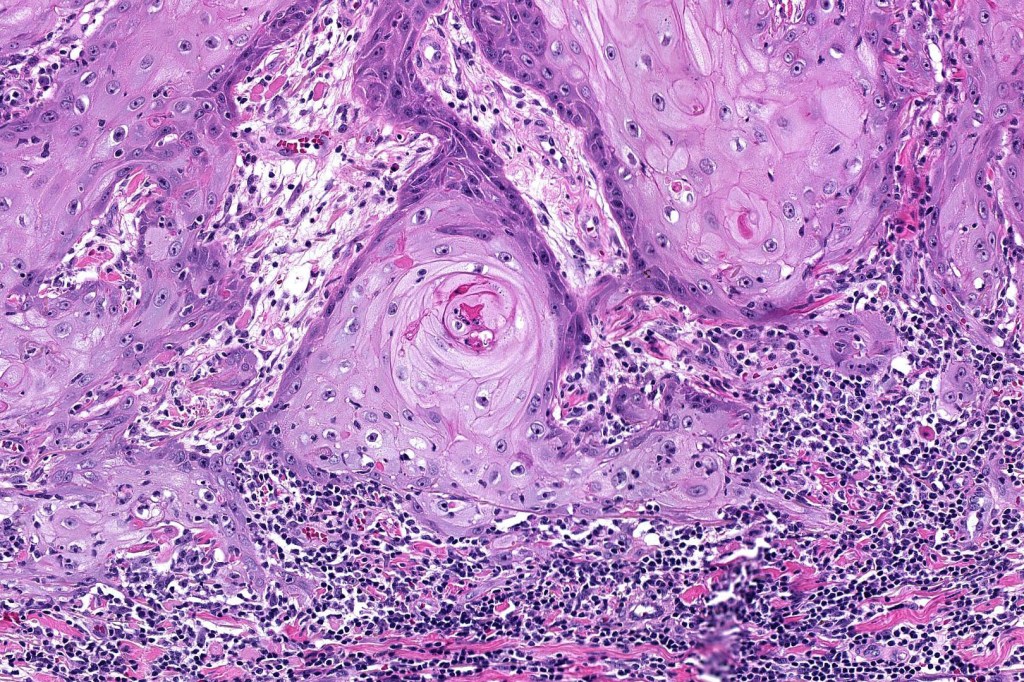

•Well differentiated squamous epithelium often with a characteristic ground-glass appearance

•Only mild pleomorphism & basally located mitoses

•Neutrophil-rich microabscesses & necrosis

Below is a fascinating case shared on McKee Derm by Dr. James Simpson. There is an obvious keratoacanthoma but at the edge of the lesion there is marked atypia with nuclear enlargement and pleomorphism. This is also evident in the adjacent epidermis and in the deeper nests.